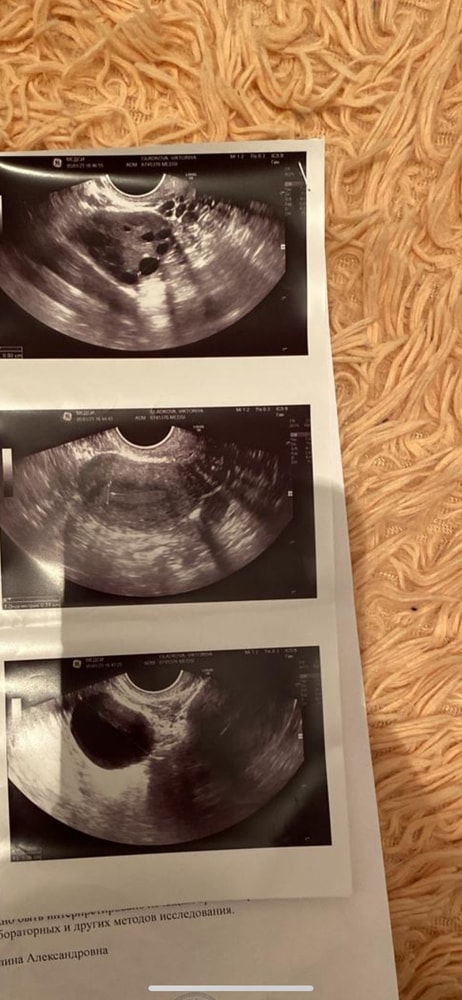

faith, делали эхо гсг и написали что там Изображение Изображение Изображение Изображение